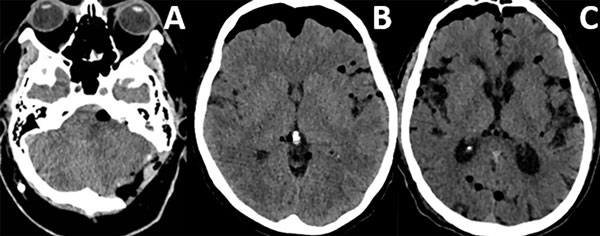

Patrones y grados de NE: NE subdural (Figura 1), se clasificó en 3 grados: leve (menor al espesor óseo), moderado (entre una vez y dos veces el espesor óseo) y severo (dos o más veces el espesor óseo). NE subaracnoideo (Figura 2), se clasificó en 3 grados: leve (confinado a cisternas basales), moderado (cisternas supratentoriales predominio unilateral), severo (generalizado). NE ventricular (Figura 3), se clasificó en: leve (en IV y/o III ventrículo), moderado (alcanzó VL), severo (alcanzó y dilató los VL).

Figura 2. Neumoencéfalo subaracnoideo. A) Leve. B) Moderado. C) Severo.